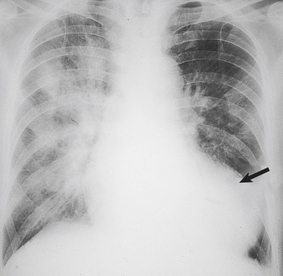

The net effect of these changes is to reduce both the strength and the elasticity of the vessel wall. Progressive dilatation is a common ageing phenomenon in both the aorta and the coronary arteries. In the ascending aorta this can lead to stretching of the aortic valve ring and aortic incompetence. Dilatation of the arch and thoracic aorta produces the characteristic ‘unfolding’ seen in chest X-rays (Fig. 13.2).

image

Fig. 13.2 Unfolding of the aorta. image There is a prominent bulge (arrow) caused by dilatation of the arch and descending aorta. If the dilatation involves the aortic valve ring, aortic incompetence may result. image Normal X-ray for comparison.